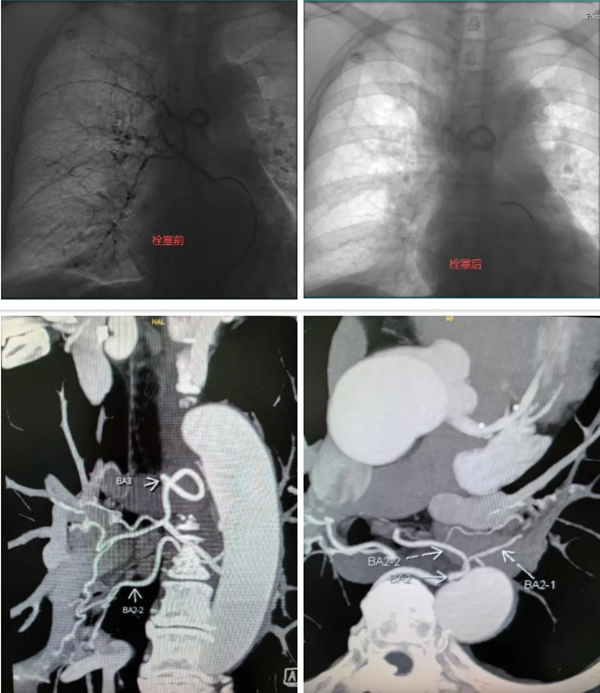

在相关科室的紧密配合下,科室迅速开始手术。手术过程中,李德志经过微导丝引导,微导管顺利超选至右侧支肋共干支气管动脉分支远端,采用PVA微球和明胶颗粒实施了有效栓塞,同时对其他异常血管,包括左侧支气管动脉分支也进行了有效的栓塞治疗,从而显著控制了患者的咯血症状。经过治疗,患者未再咯血,病情稳定后顺利康复出院。

一位有既往结核病引起咯血病史的患者,五年前接受了支气管动脉栓塞术,患者因咳嗽伴痰中带血症状持续超过一个月,为获得进一步的治疗再次入院。入院后支气管动脉CTA检查显示,患者之前栓塞所用的弹簧圈如同拦路虎一般,横亘在右侧支气管与肋间动脉共干的主干近端。科室会诊讨论制定手术方案,提前预判手术难度,确定用微导管超选越过既往栓塞的弹簧圈,到达右侧支肋共干支气管动脉的远端分支进行有效栓塞。

征得患者家属同意后,李德志进行手术。他在助手默契配合下,经过多次尝试,在微导丝引导下成功将微导管超选越过既往栓塞的弹簧圈,顺利到达右侧支肋共干支气管动脉的远端分支,利用PVA微球和明胶颗粒,实现了有效的栓塞治疗。手术中,李德志对其他异常血管,包括左右共干支气管动脉、右侧胸廓内动脉发出的异位支气管动脉以及食管固有动脉分支进行了栓塞,最终取得了满意的临床治疗效果。患者顺利康复出院。